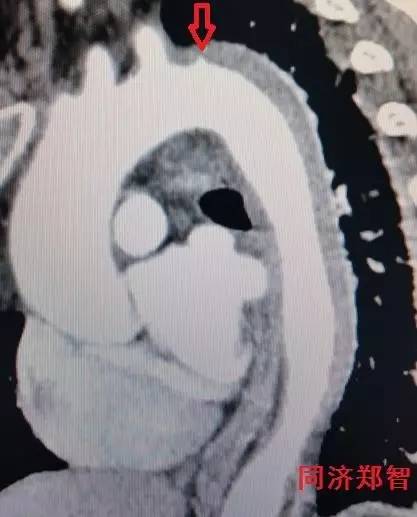

② Stanford A型 主动脉壁间血肿的CTA重建(图2),提示升主动脉和胸降主动脉的主动脉壁均有病变(红箭头所示)。

图2